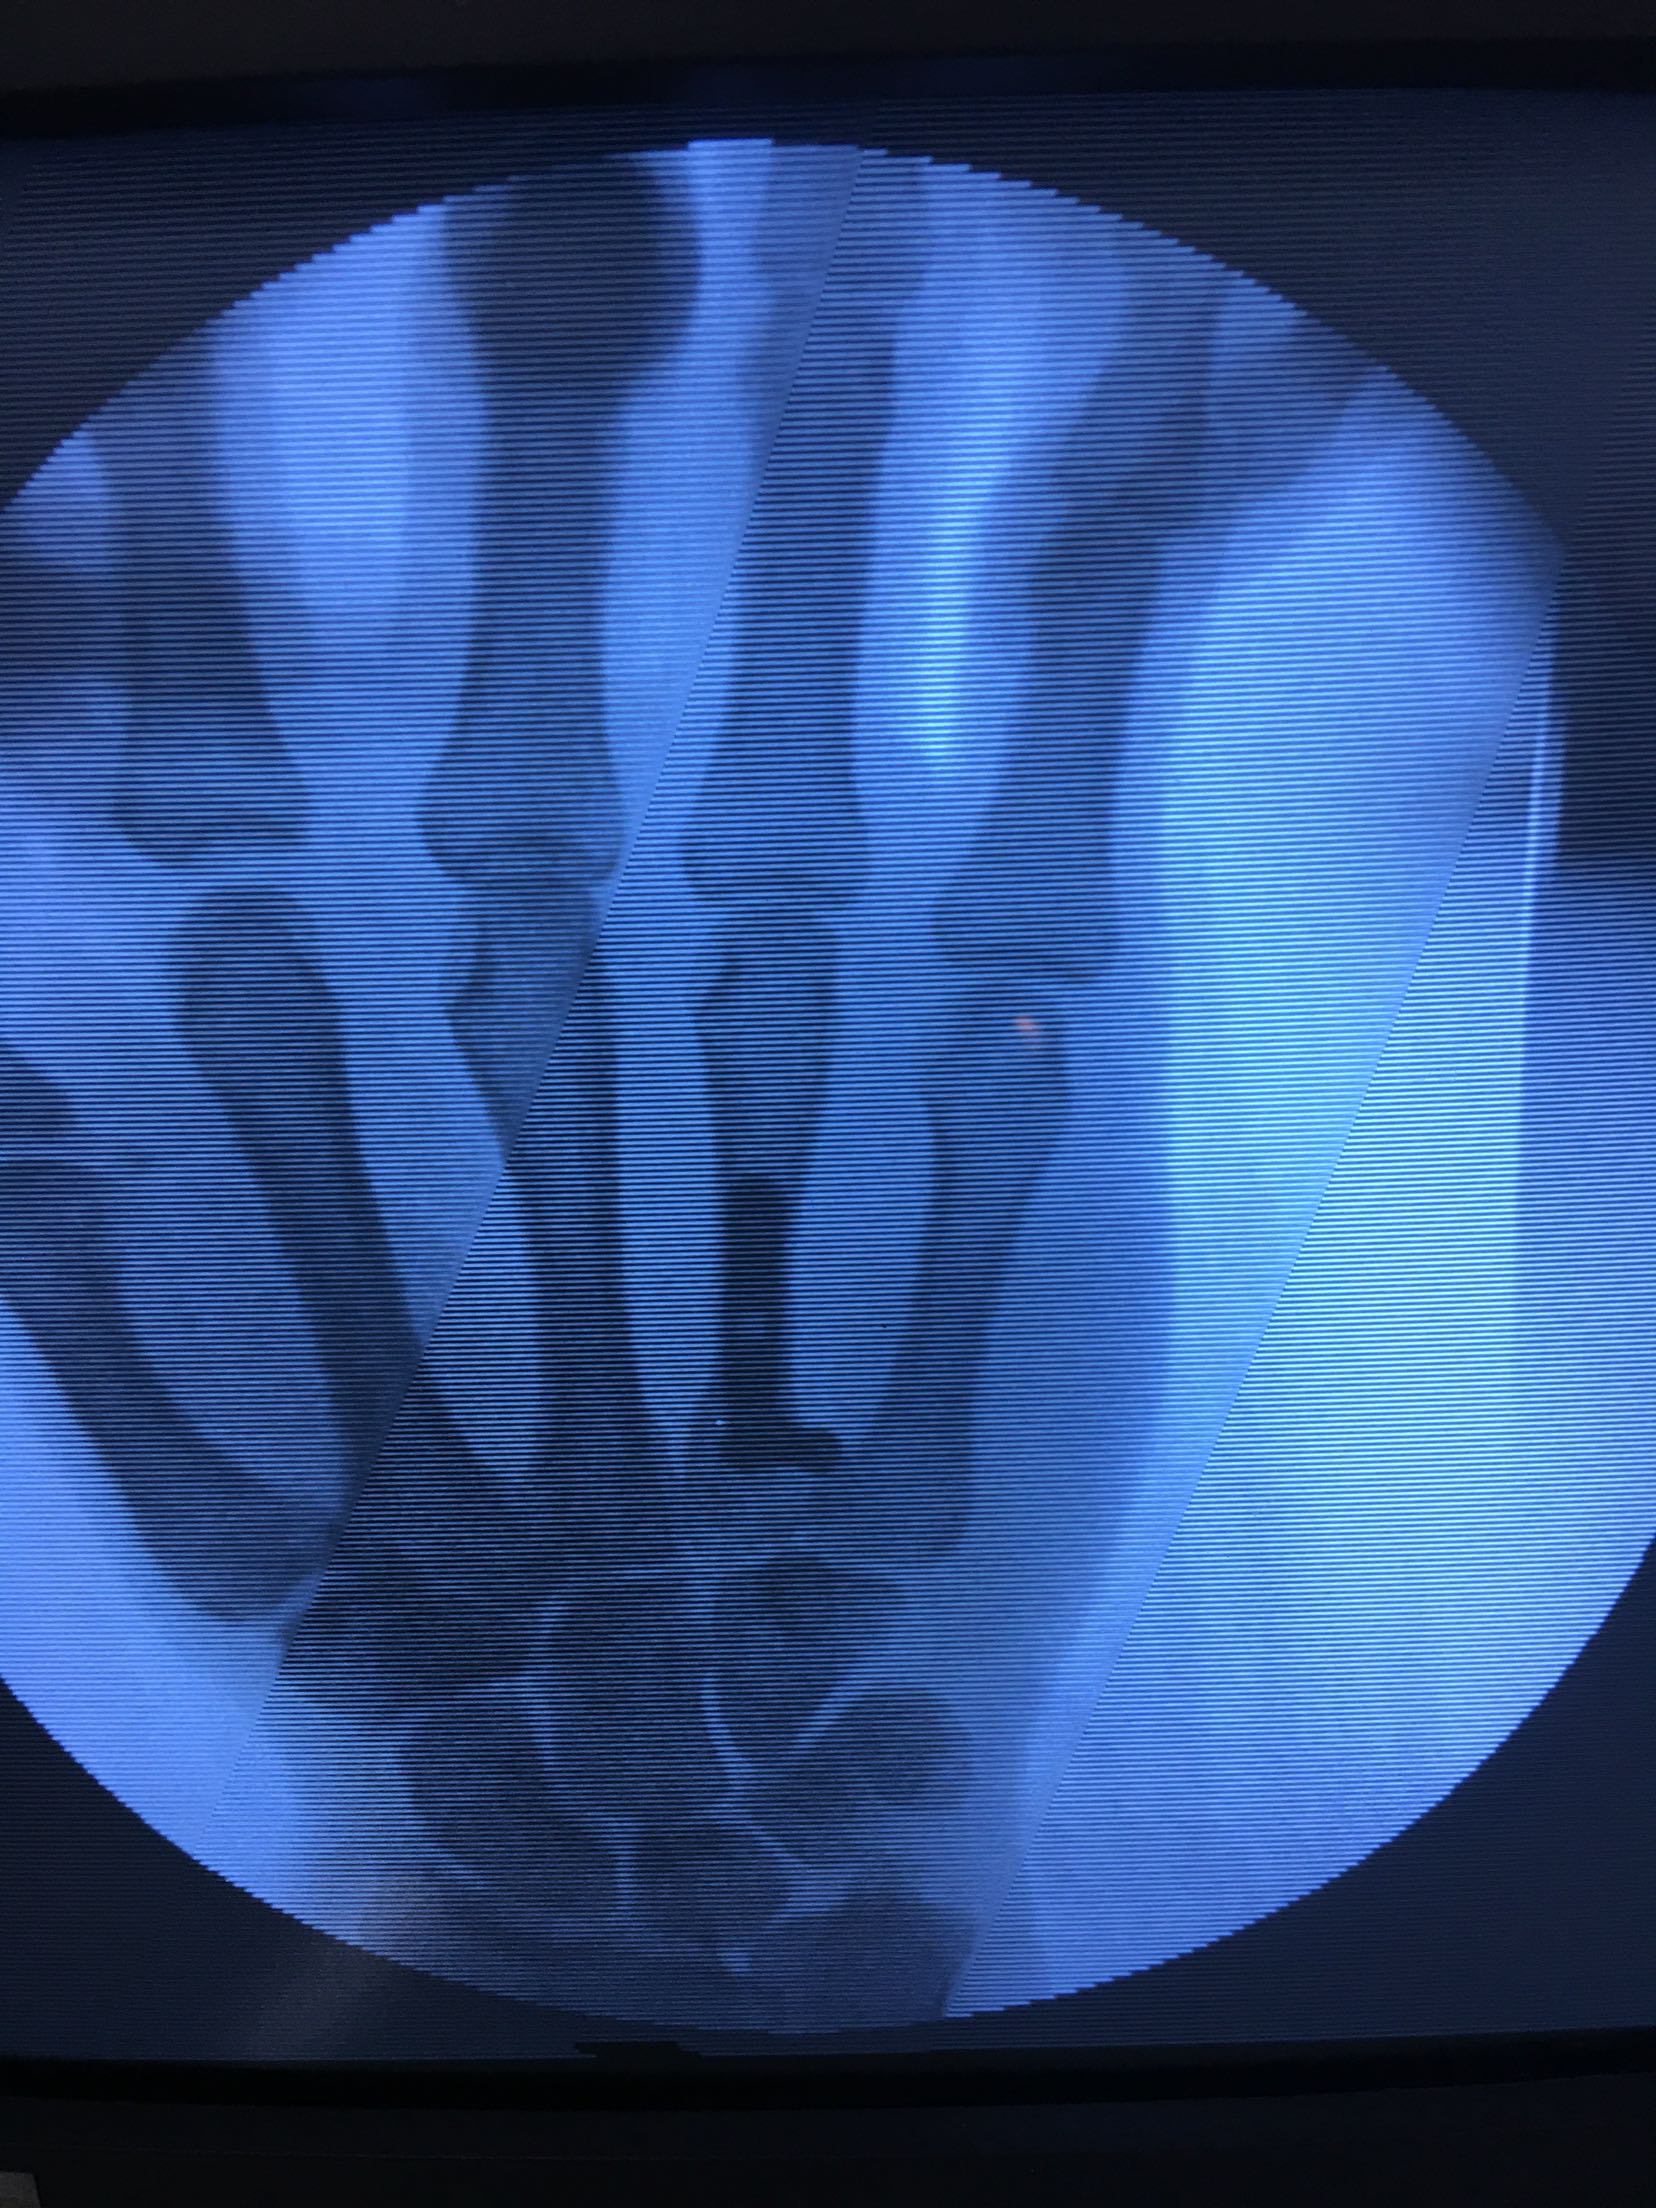

患者,男,52岁,摔伤后右手肿痛,活动受限4小时入院。

右手掌肿胀明显,皮色皮温正常,局部压痛,纵叩痛阳性,可及骨擦感,第四掌指关节活动受限,末梢血运感觉正常。

完善检查,在臂丛麻醉下行切复内固定术,术后抗炎,消肿止痛处理。